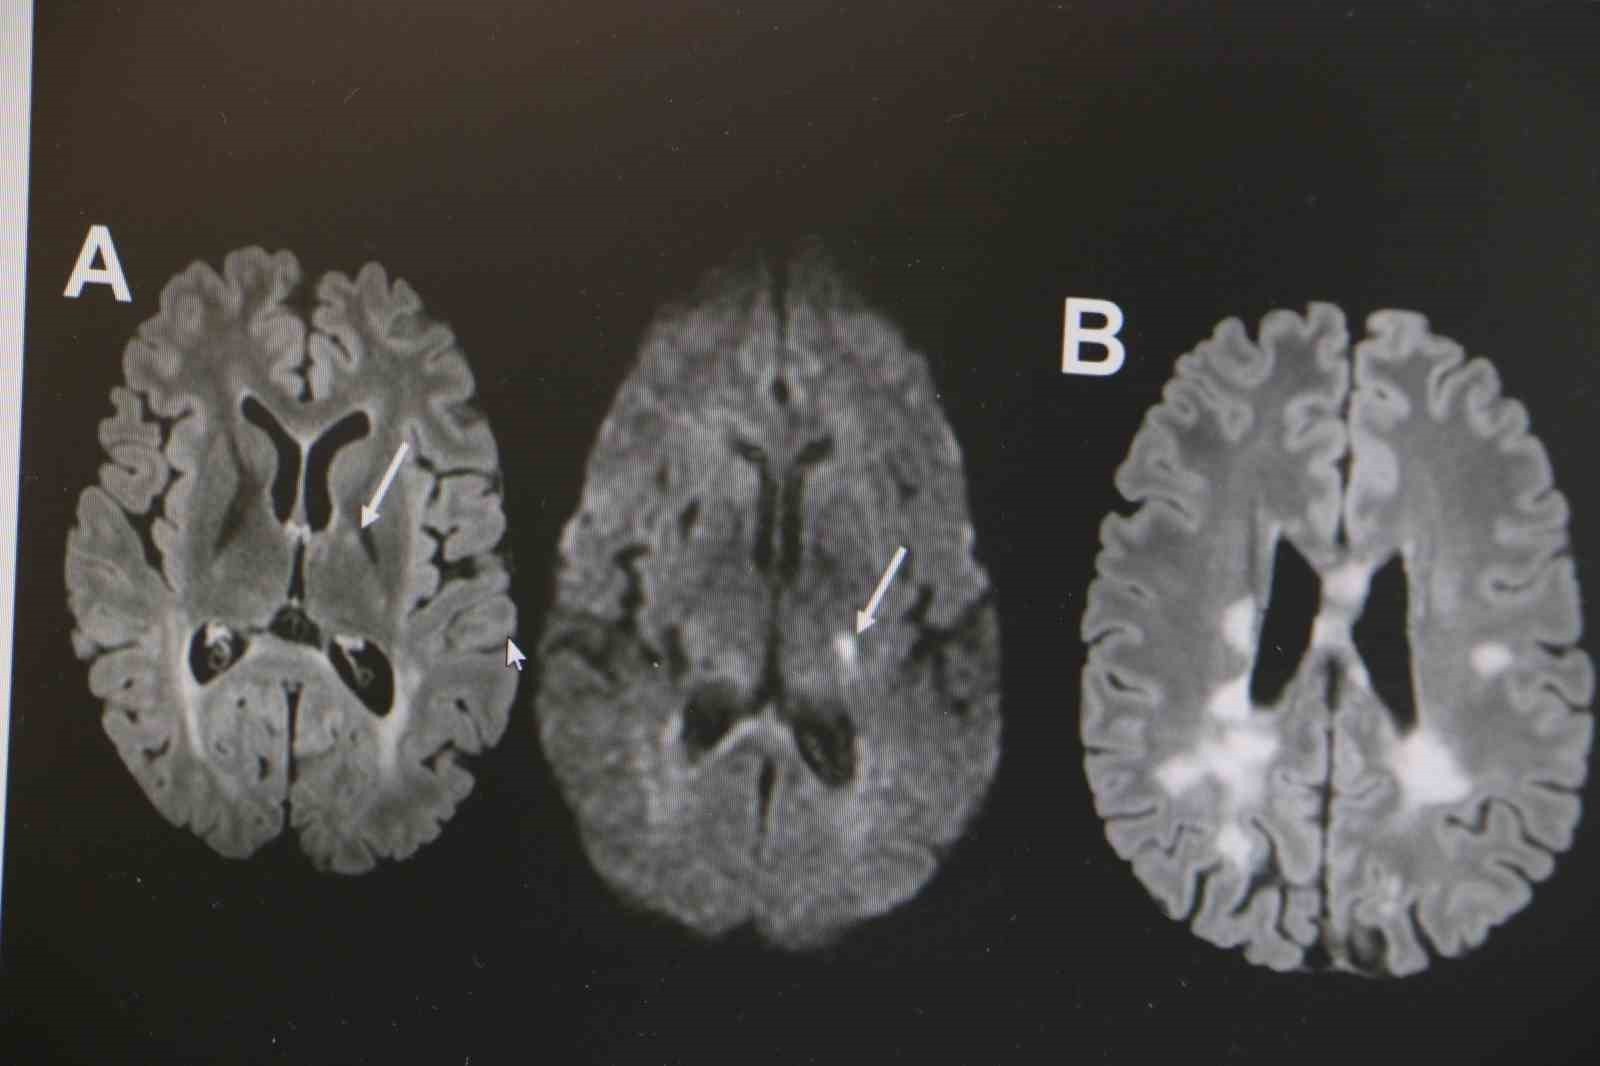

Diyarbakır Selahaddin Eyyubi Devlet Hastanesinde Nöroloji Uzmanı Dr. Fidel Demir, Uluslararası Multiple Skleroz (MS) Federasyonu’na göre dünyada 3 milyona yakın MS hastasının bulunduğunu ve 60 bininin Türkiye’de olduğunu söyledi. Nöroloji Uzmanı Dr. Fidel Demir, 30 Mayıs "Dünya MS Günü" dolayısıyla İhlas Haber Ajansı (İHA) muhabirine, MS hastalığı sıklığının gittikçe arttığını söyledi. MS hastalığının otoimmün bir hastalık olduğunu belirten Dr. Demir, "Vücuttaki bağışıklık sisteminin beyindeki sinir hücrelerinin yalıtımını sağlayan sinir kılıfına, beyin hücrelerine saldırması sonucu beyinde hasar oluşmaktadır. Hastalığın isminden de anlaşılacağı üzere MS hastalığı birçok bölgede skar dokusuna sebep olabilmektedir. Özellikle hastalarda kol ve bacaklarda güçsüzlük, uyuşmalar, görme kayıpları, baş dönmesi, çift görmeler gibi birçok nörolojik belirti oluşabilmekte. Uluslararası MS federasyonuna göre dünyada 3 milyona yakın MS hastası bulunmakta. Her 5 dakikada bir MS hastalığı tanısı koyulmaktadır. Ülkemizde de yaklaşık 60 bin MS hastası bulunmakta. MS hastalığı ekvatordan uzaklara gidilen ülkelerde, özellikle Avrupa ülkeleri, Amerika ve Kanada gibi ülkelerde sıklığı gittikçe artmakta" dedi. MS hastalığının kadın popülasyonunda daha sık görüldüğünün altını çizen Demir, "Kadınlarda erkeklere göre bu hastalık yaklaşık 2 kat daha sık görülmekte. MS hastalığı özellikle ataklarla seyreden bir hastalıktır. Hastaların yüzde 85’inde relapsing remitting form dediğimiz atak formuyla seyretmektedir. MS hastalığının tanısı klinik olarak kesin tanı konulabilse de günümüz şartlarında MR çekilmeden kesin tanı konulmaması önerilmektedir. MS hastalığının tedavisine gelecek olursak, kesin bir tedavisi yoktur. Ancak son 10 yılda çok sayıda ilaç kullanıma girmiştir. Bu açıdan MS hastalığı kontrol edilebilir bir hastalıktır. MS hastalığına bağlı ataklara karşı hastalara steroid tedavisi vermekteyiz. MS hastalarında görülen her şikayet atak olmayabilir. Özellikle idrar yolu enfeksiyonu, üst solunum yolu enfeksiyonu, aşırı egzersiz durumlarında, sıcak bir ortamda bulunma gibi durumda hastalarda ısı artışına bağlı olarak daha önceden var olan semptomlarda kötüleşme olabilir. Bunlar daha çok yalancı atak diyebiliriz. Ancak atak diyebilmemiz için şikayetin en az 24 saat sürmesi gerekmektedir" ifadelerinde bulundu. MS hastalarının vitamin takviyesi yapması gerektiği yönünde uyarıda bulunan Demir, son olarak şunları kaydetti: "MS hastalarının kesinlikle sigara içmemeleri gerek. Çünkü sigara hastanın tedavi başarısını düşürmektedir. MS hastalarına vitamin D takviyesi önermekteyiz. Çünkü vitamin D eksikliği olan hastalarda beyinde lezyon yükü artışı olur. Prognoz olumsuz etkilenir. Atakların kontrol altına alınması zorlaşır. MS hastalarında D vitamini düzeyinin 40 ng/ml üzerinde olmasını öneriyoruz. Bu yüzden D vitamini takviyesi oldukça önemlidir."